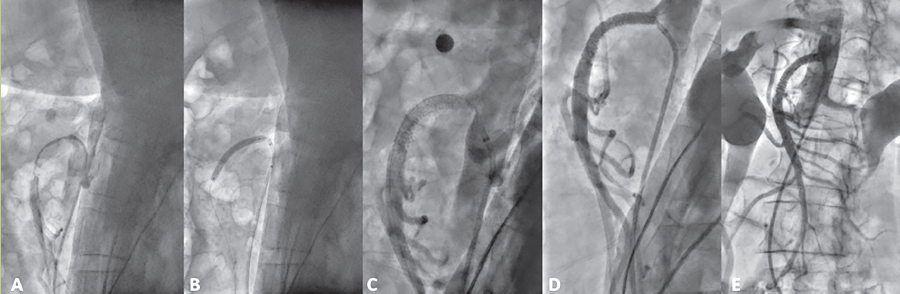

Después de los hallazgos previos, se decidió tratamiento endovascular; se proyectó angioplastia mesentérica superior con duración de 3 horas con abordaje femoral, previa medicación con clopidogrel 75 mg5 y ASA 100 mg5. Se canalizó femoral, se pasó guía y catéter de cola de cochino, al llegar a t12 se realizó angiografía de aorta abdominal, visualizándose oclusión total de la mesentérica superior, se observó oclusión de 40% en tronco celiaco, se realizó angioplastia en mesentérica superior con balones y colocación de 3 stents en mesentérica superior (figura 4a-e).

Figura 4 Angiografía que muestra inicialmente defecto de llenado en el nacimiento de la arteria mesentérica superior (a), con recanalización parcial de la misma, posteriormente dilatación con balón (b). Apertura y colocación de stent (c) en el sitio del defecto. Tras la administración del medio de contraste se observa recanalización total de la mesentérica superior (d) y de sus ramas pancreaticoduodenal inferior, yeyunales, ileales, cólica derecha inferior y superior y cólica media (e).